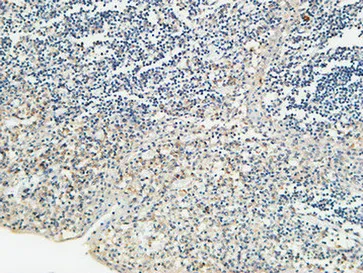

CD68 Rabbit Polyclonal Antibody

Cat: APRab08436